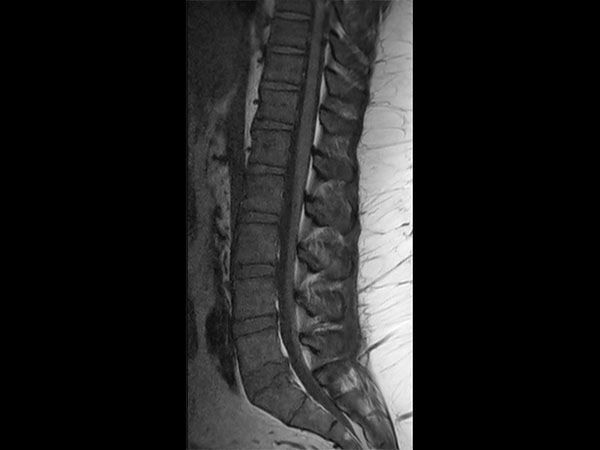

Lumbar Spine - Obese patient

32- year old male patient, 180 kg, with back pain. Was first examined on CT but quality was not sufficient for diagnosis. MRI gave excellent images. Diagnosis: small protrusion of the disc L5/S1, no meningioma.